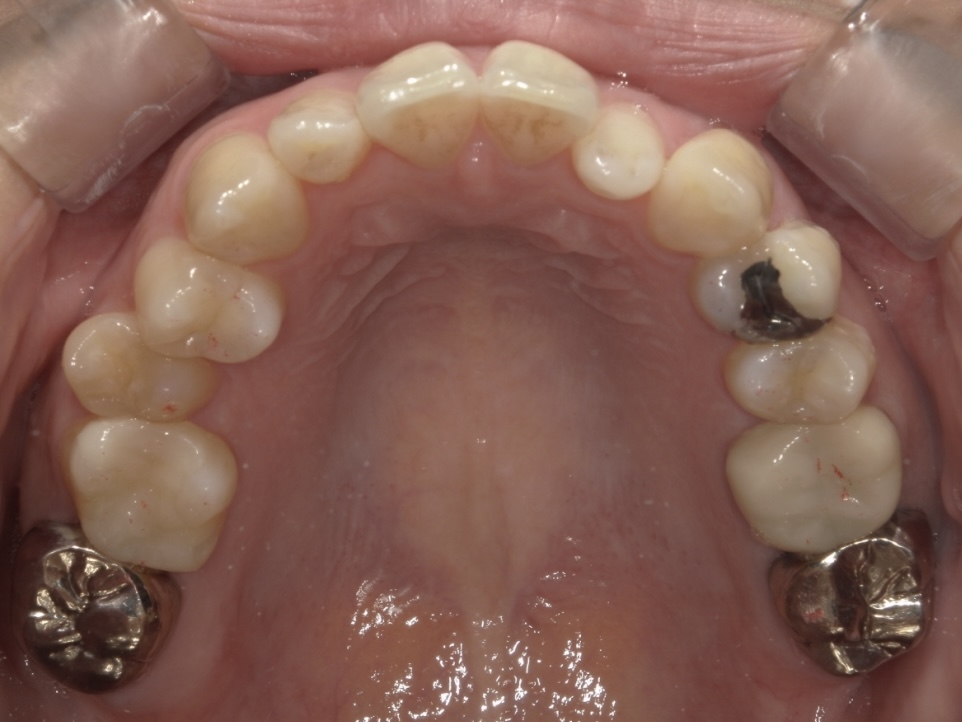

30代女性 ガタガタが気になる

長年歯並びに悩まれており、遠方よりご相談にいらしてくださいました。2年という期間で綺麗な歯並びに整えることができた症例です。

BEFORE